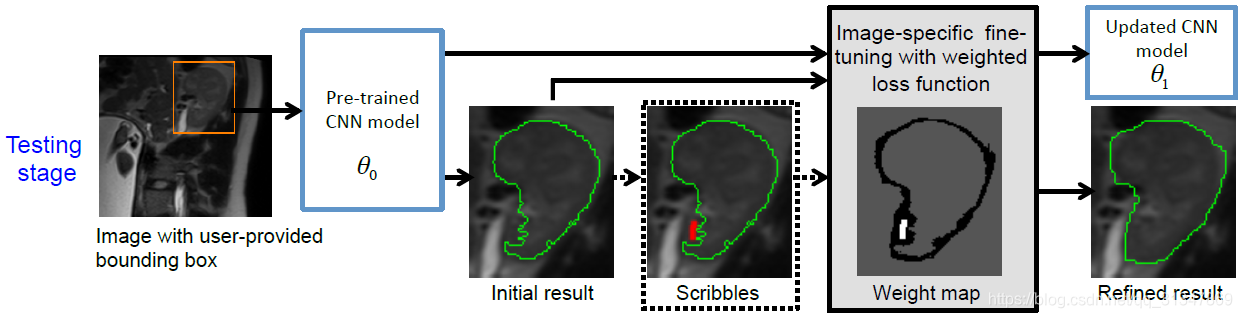

测试过程:

测试时,由用户提供一个 bbox,输入训练好的 CNN 模型中(参数为

θ

0

\theta_0

θ0)可以得到一个初始的分割结果(Initial result),再由用户进行有监督的微调或无监督的微调(Scribbles),对初始的分割结果进行调整,得到一个更新后的 CNN 模型(参数为

θ

1

\theta_1

θ1,Refined result)

【在测试阶段需要用户提供 bounding box,但是也可以研究一下自动生成 bbox 来进一步提高效率】

在第一步训练好 CNN 模型参数 θ 0 \theta_0 θ0 以后,接着就在测试阶段对模型进行 fine-tuning,也就是更新参数 θ 0 \theta_0 θ0,最终要得到更新后的参数 θ 1 \theta_1 θ1。

在测试阶段,用户为测试图像提供一个 bounding box 然后输入到训练好的 CNN model ( θ 0 \theta_0 θ0 ) 中,CNN 根据 bbox 得出一个初步的分割结果 Y ^ 0 \hat Y_0 Y^0。

接着对分割结果 Y ^ 0 \hat Y_0 Y^0 进行有监督或无监督的 fine-tuning,即画一些修正的 scribbles,根据这些 scribbles 对结果再修改。